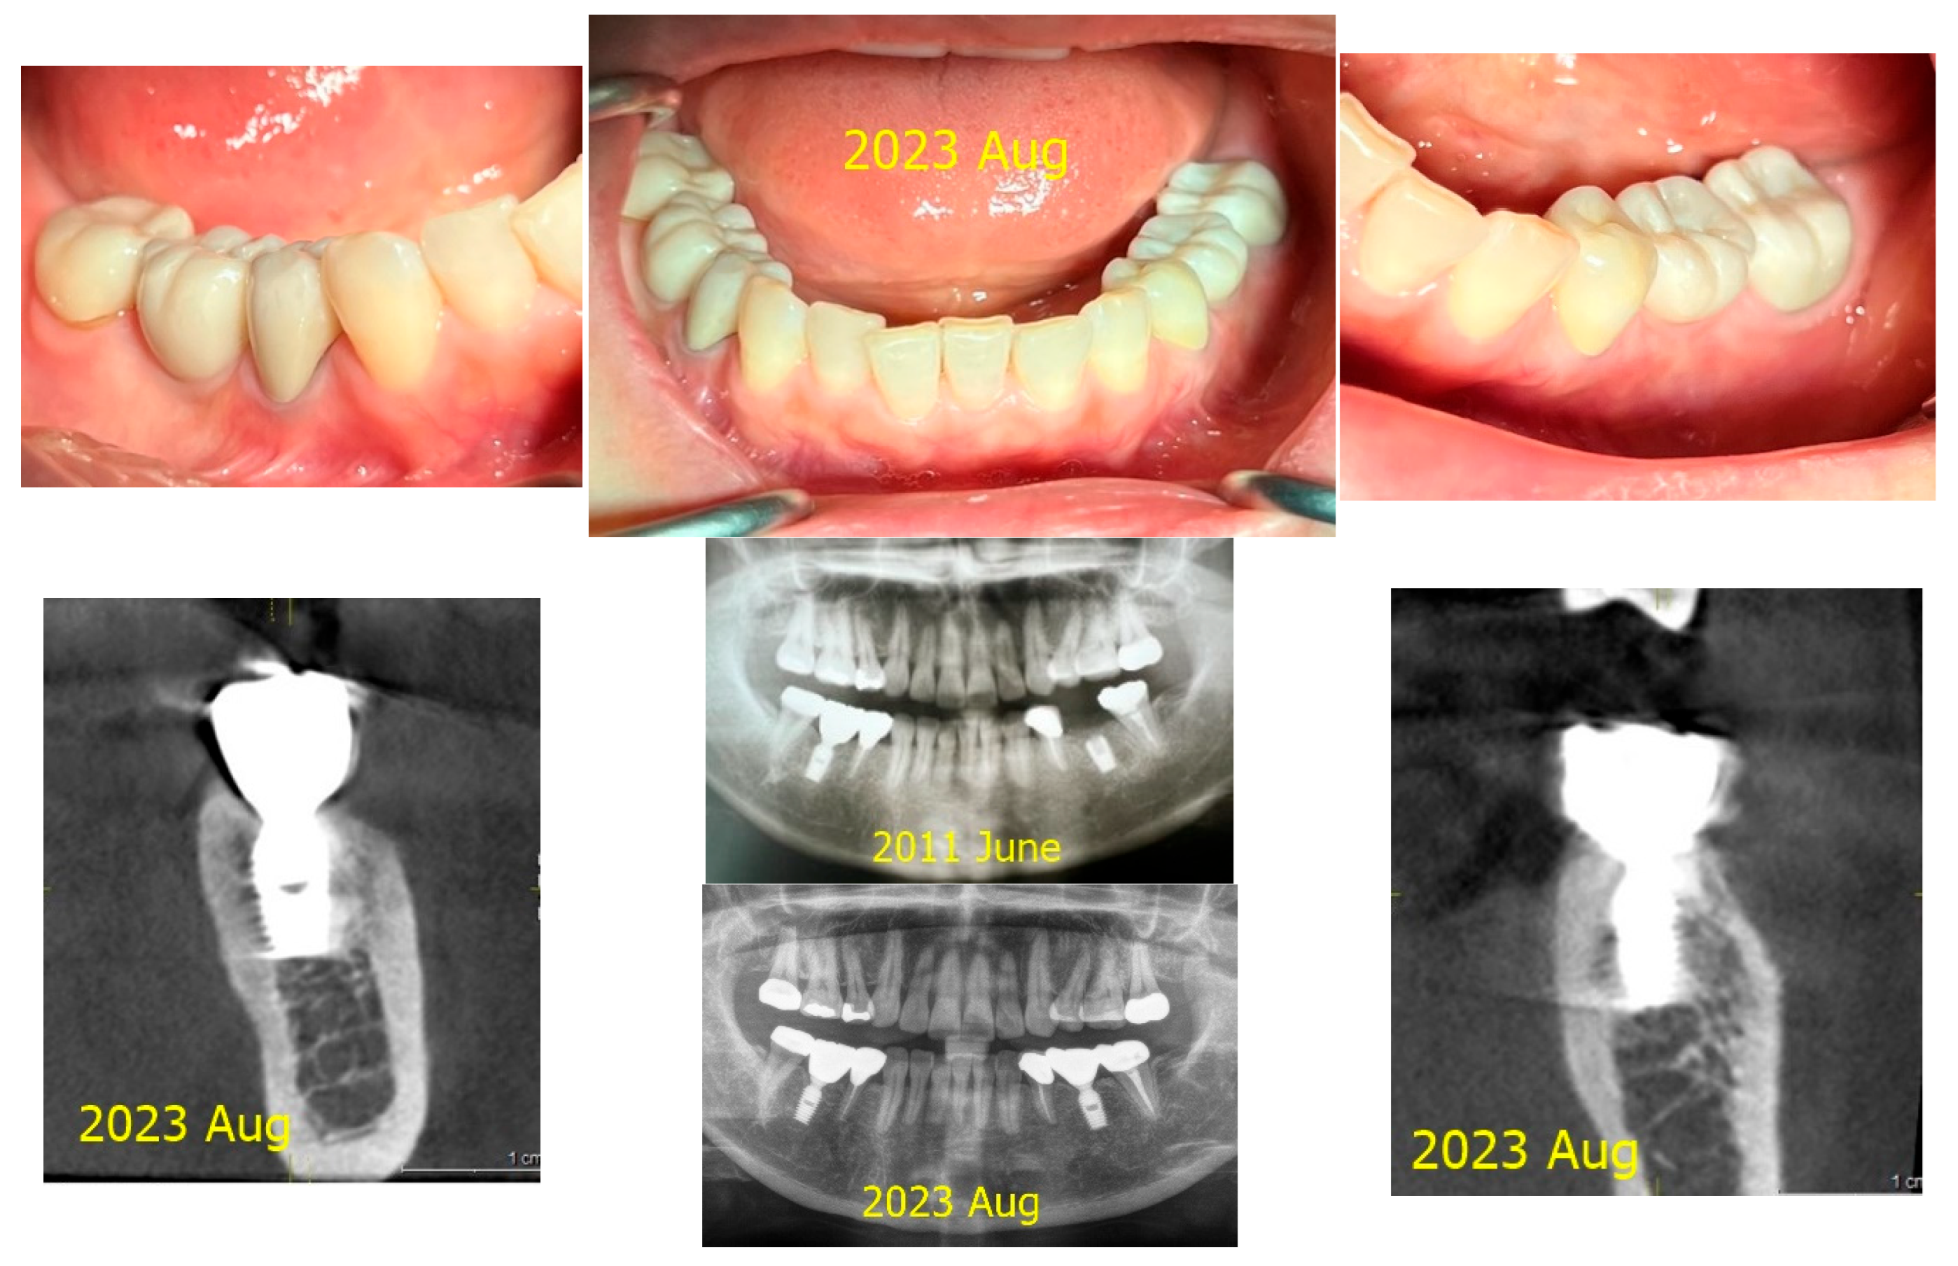

These two implant sites serve as a comparison for a split-mouth study. CBCT scans taken in 2021 and 2024 were utilized for a three-dimensional analysis of peri-implant soft tissue and bone structure.

Measurements of CRD changes for both implant sites (control and treatment) were conducted using Cone Beam Computed Tomography (CBCT). The analysis focused on parameters such as Crest to Restoration Distance (CRD), Depth of Placement (DP), and other structural features using CBCT imaging, complemented by clinical assessments. The primary objective was to evaluate how changes in CRD correlate with peri-implant health and disease, particularly in managing peri-implant mucositis.

Figure 7 and Figure 8 illustrate the radiographic changes observed from 2021 to 2024 at the lower right first molar implant site (control site) and the upper left first molar implant site (experimental site), respectively. (Figure 7, Figure 8) The clinical photographs taken in 2024 (Figure 9) depict the final results, showcasing both a stable and natural appearance for both implant sites.

Figure 7. This image illustrates the X-ray measurements conducted on the lower right first molar implant, comparing data from 2021 and 2024.

Preprints 151394 g007

Figure 8. This image illustrates the X-ray measurements conducted on the upper left first molar implant, comparing data from 2021 and 2024..

Preprints 151394 g008